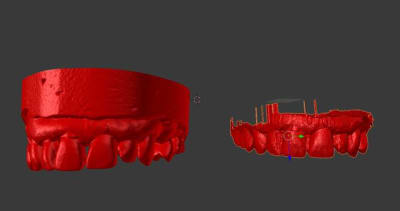

première tentative d'importation du .cdt

il y a apparemment enchevêtrement des différentes saisies et un pb de nettoyage qui n'est pas pris en compte comme il devrait à ce stade de la modélisation du .cdt.

L'empreinte optique vestibulaire de l'occlusion génère à mon avis les artefacts que l'on voit sous forme de "pics" dans le sens LV... Apparament pas de trace de la restauration finale. Je dois faire plus de tests et je repasse ici d'ici quelques temps ...